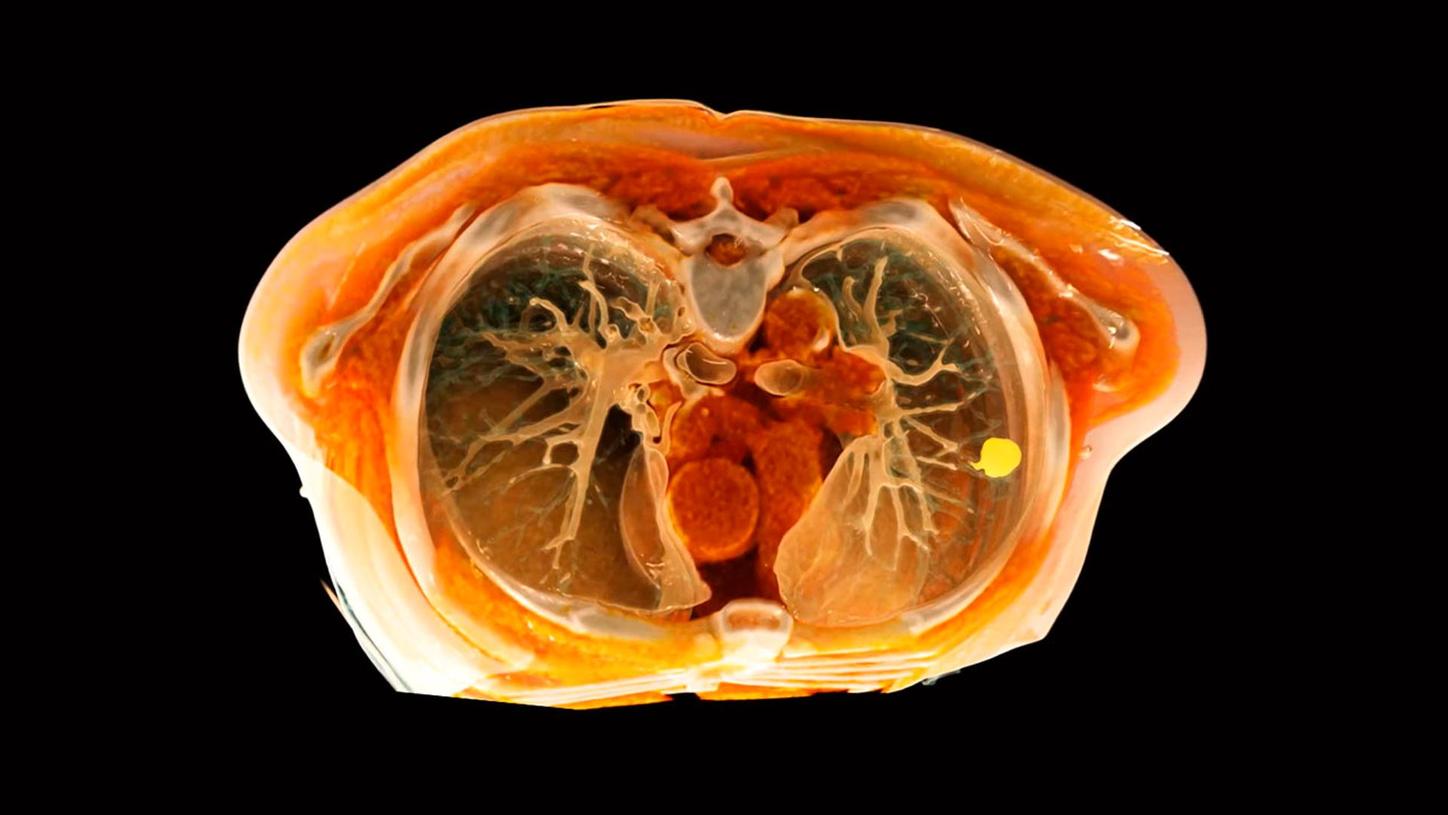

Already today, we cover many clinical topics and tailor our radiology products and solutions along clinical pathways. With intelligent, digitally connected imaging solutions you can improve diagnostic accuracy, plan treatment options and guide minimally invasive therapy. With our focus towards the world’s major diseases including stroke, coronary artery disease, lung, and liver cancer, we are committed to supporting patients in every step of their journey.